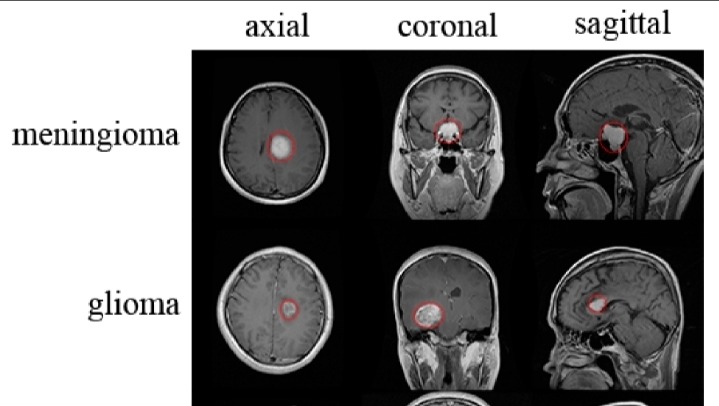

Just a few months ago, Sachin started experiencing severe headaches and weakness in his arms and legs. After tests at Scarborough Health Network, an MRI revealed a devastating diagnosis: a large left cerebellar mass, measuring about 4.5 x 5.5 x 4.4 cm, involving key areas of the brain like the left middle cerebellar peduncle and pons. This tumor is compressing critical structures, including the fourth ventricle and brainstem, causing displacement and mild hydrocephalus (buildup of fluid in the brain). The doctors have described it as an aggressive tumor requiring immediate and intensive treatment, consistent with a high-grade (stage 4) brain tumor.